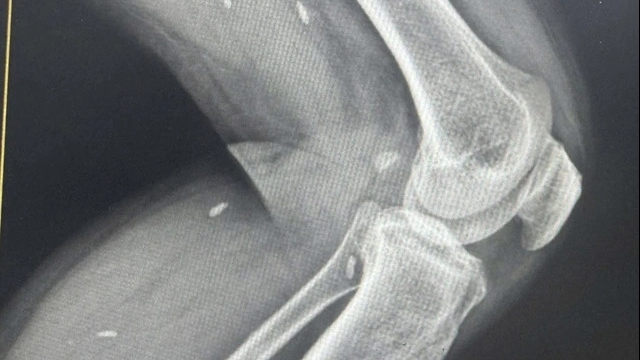

Cách điều trị và dự phòng bệnh dại duy nhất và hiệu quả nhất là tiêm vaccine. |